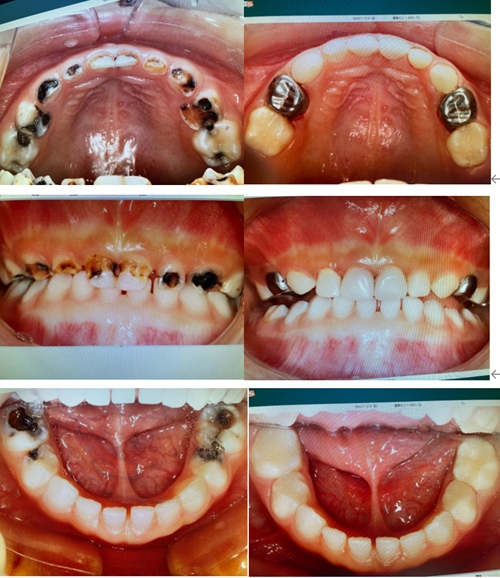

張開(kāi)嘴竟有14顆爛牙,4歲女童一覺(jué)醒來(lái)“爛牙”變“白牙”

悅悅的大眼睛撲閃撲閃很可愛(ài),可是一張口,牙齒已齲壞變黑,這令她有些不自信,平日里也不太愿意笑。針對(duì)患兒病情,城陽(yáng)院區(qū)口腔科醫(yī)護(hù)人員精心配合,對(duì)悅悅的14顆牙齒進(jìn)行了全麻下治療;并對(duì)前牙進(jìn)行了美容冠修復(fù)以及后牙的金屬預(yù)成冠修復(fù)。

“一點(diǎn)也不疼,媽媽”,美美睡了一覺(jué)后,悅悅看著鏡子里的一口小白牙開(kāi)心的笑了。手術(shù)后,經(jīng)過(guò)牙齒充填和冠修復(fù)的牙齒變漂亮了,悅悅的爸媽高興地合不攏嘴。第二天家長(zhǎng)辦完了出院手續(xù),又特意帶孩子到門(mén)診感謝?!疤x謝您了!我們都可滿(mǎn)意了!”